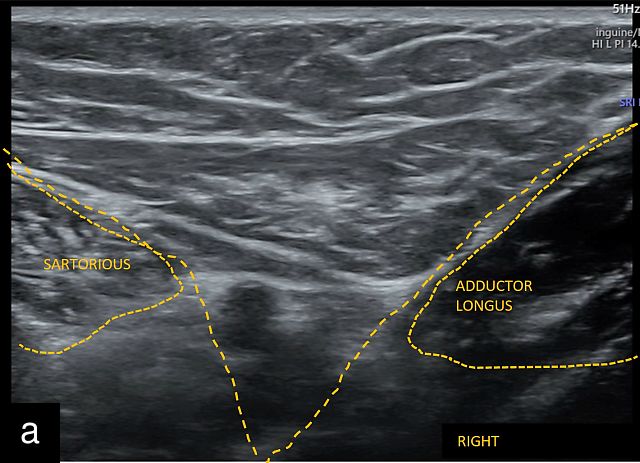

- the apex of the femoral triangle, located at the intersection of the sartorius and adductor longus muscles (‘V sign’) (Figure 1a)

![]() | ![]() | ![]() |

Anatomical landmarks for location of the inguinal lymph nodes on ultrasound. (a) Valley or V sign. (b) Snail sign. (c) Hill sign. EIA, external iliac artery; EIV, external iliac vein; FA, femoral artery; FV, femoral vein; PT, pubic tubercle